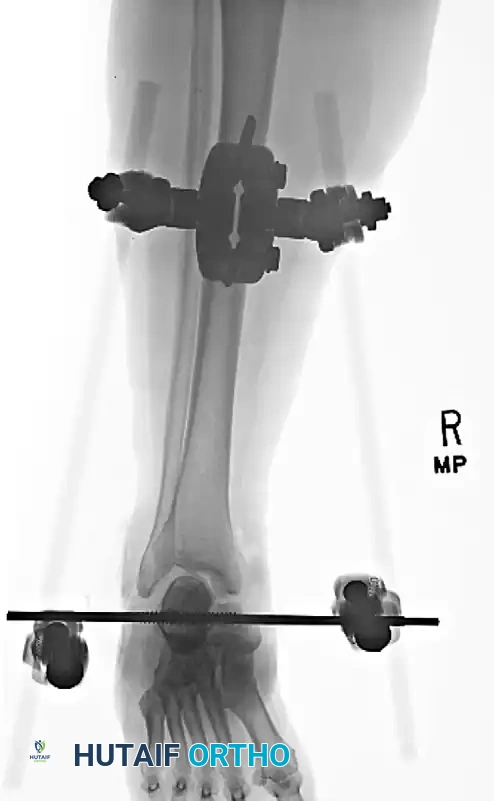

MANAGEMENT OF SEVERE OPEN DISLOCATIONS

Patients with open fractures and associated fractures generally have a significantly poorer prognosis than those with isolated closed dislocations. High-energy open peritalar dislocations are fraught with complications, including deep infection, massive soft tissue loss, and a high rate of talar osteonecrosis (occurring in up to one-third of severe cases).

External Fixation

In cases of severe soft tissue swelling, gross instability post-reduction, or open injuries requiring serial debridement, spanning external fixation is the treatment of choice. A delta frame or a medial spanning fixator (tibia to first metatarsal and calcaneus) maintains length, alignment, and joint congruity while allowing access for wound care.

Application of a spanning external fixator to hold the reduction and stabilize the soft tissue envelope in a severe open dislocation.